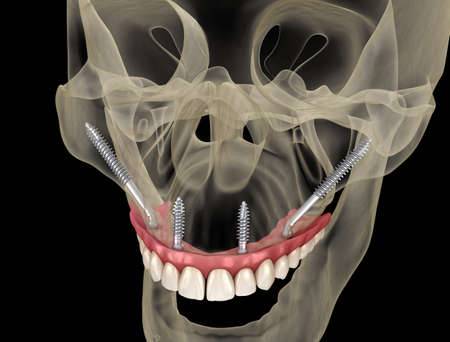

L'implant zygomatique, également connu sous le nom d'implant malaire, est une option de traitement utilisée au cabinet Implantys près de Mâcon pour ancrer des prothèses dentaires chez les patients qui ont une perte osseuse sévère dans la région maxillaire supérieure et qui ne peuvent pas bénéficier d'implants conventionnels en raison du manque de densité osseuse. L'implant zygomatique diffère donc des implants dentaires conventionnels qui sont, eux, insérés dans l'os maxillaire. Cet implant est conçu pour être fixé dans l'os zygomatique, également appelé os malaire, situé près de la pommette. Cette alternative vous est proposée par nos chirurgiens dentistes spécialisés en implantologie, au cabinet Implantys proche de Belleville-en-Beaujolais.

Le processus d'implantation zygomatique est plus complexe que celui des implants conventionnels. Il nécessite une évaluation et une planification approfondies, ainsi qu'une intervention chirurgicale réalisée par un spécialiste qualifié, comme vous en trouverez dans notre au cabinet Implantys près de Belleville-en-Beaujolais. Pendant la chirurgie réalisée sous anesthésie générale, l'implant zygomatique est fixé à l'os zygomatique de manière à fournir une base solide pour les prothèses dentaires, telles que les bridges ou les prothèses complètes.